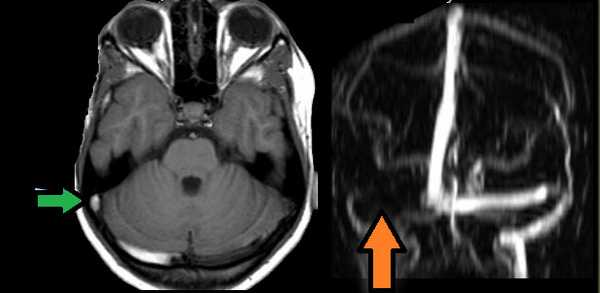

МРТ головного мозга: отмечается сочетание вазогенного (оранжевая стрелка), цитотоксического отека и кровоизлияния (зеленая стрелка). Данная МР-картина, а также расположение патологической зоны в проекции височной доли, заставляет задуматься о геморрагическом венозном НМК вследствие тромбоза вены Лаббе. Для подтверждения необходимо проведение МР-венографии или МРТ с контрастным усилением.